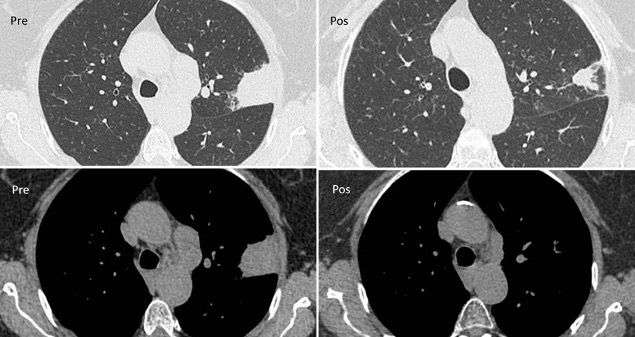

In an asymptomatic 77-year-old woman, former 55 pack-years smoker, a routine X-ray showed a 45-mm superior left lobe lesion (Figure 1). A chest CT scan confirmed a 36-mm superior left lobe lesion and an aortic-pulmonary lymph node enlargement measuring 42 mm, suspicious for neoplasia (Figure 2). A PET-CT scan showed an elevated uptake in the primary lesion, in the aortic-pulmonary lymph node, and in the left hilar lymph node with a standardized uptake value – 40 and 4.3, respectively (Figure 3).

After multidisciplinary team consultation, the patient received radiotherapy (Figure 4) with concurrent weekly paclitaxel and carboplatin. The treatment was well tolerated, and the patient had no toxicity. A CT scan after therapy showed a good response (Figure 5). After chemo-radiotherapy treatment, the patient started durvalumab as consolidation therapy.

Figure 2. CT scan with pulmonary lesion and mediastinal lymph node.

Figure 5. CT scan prior to radiochemotherapy and post radiochemotherapy.